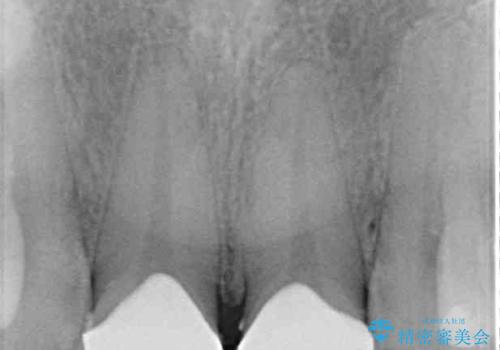

- 上顎2前歯の色を気にして来院された患者様です。

2本ともに虫歯治療による充填材の変色などによりつぎはぎのような前歯となっていたため、オールセラミッククラウンにて補綴治療を行うこととしました。

今後ホワイトニングをする予定とのことで、少し明るめのトーンに仕上げました。